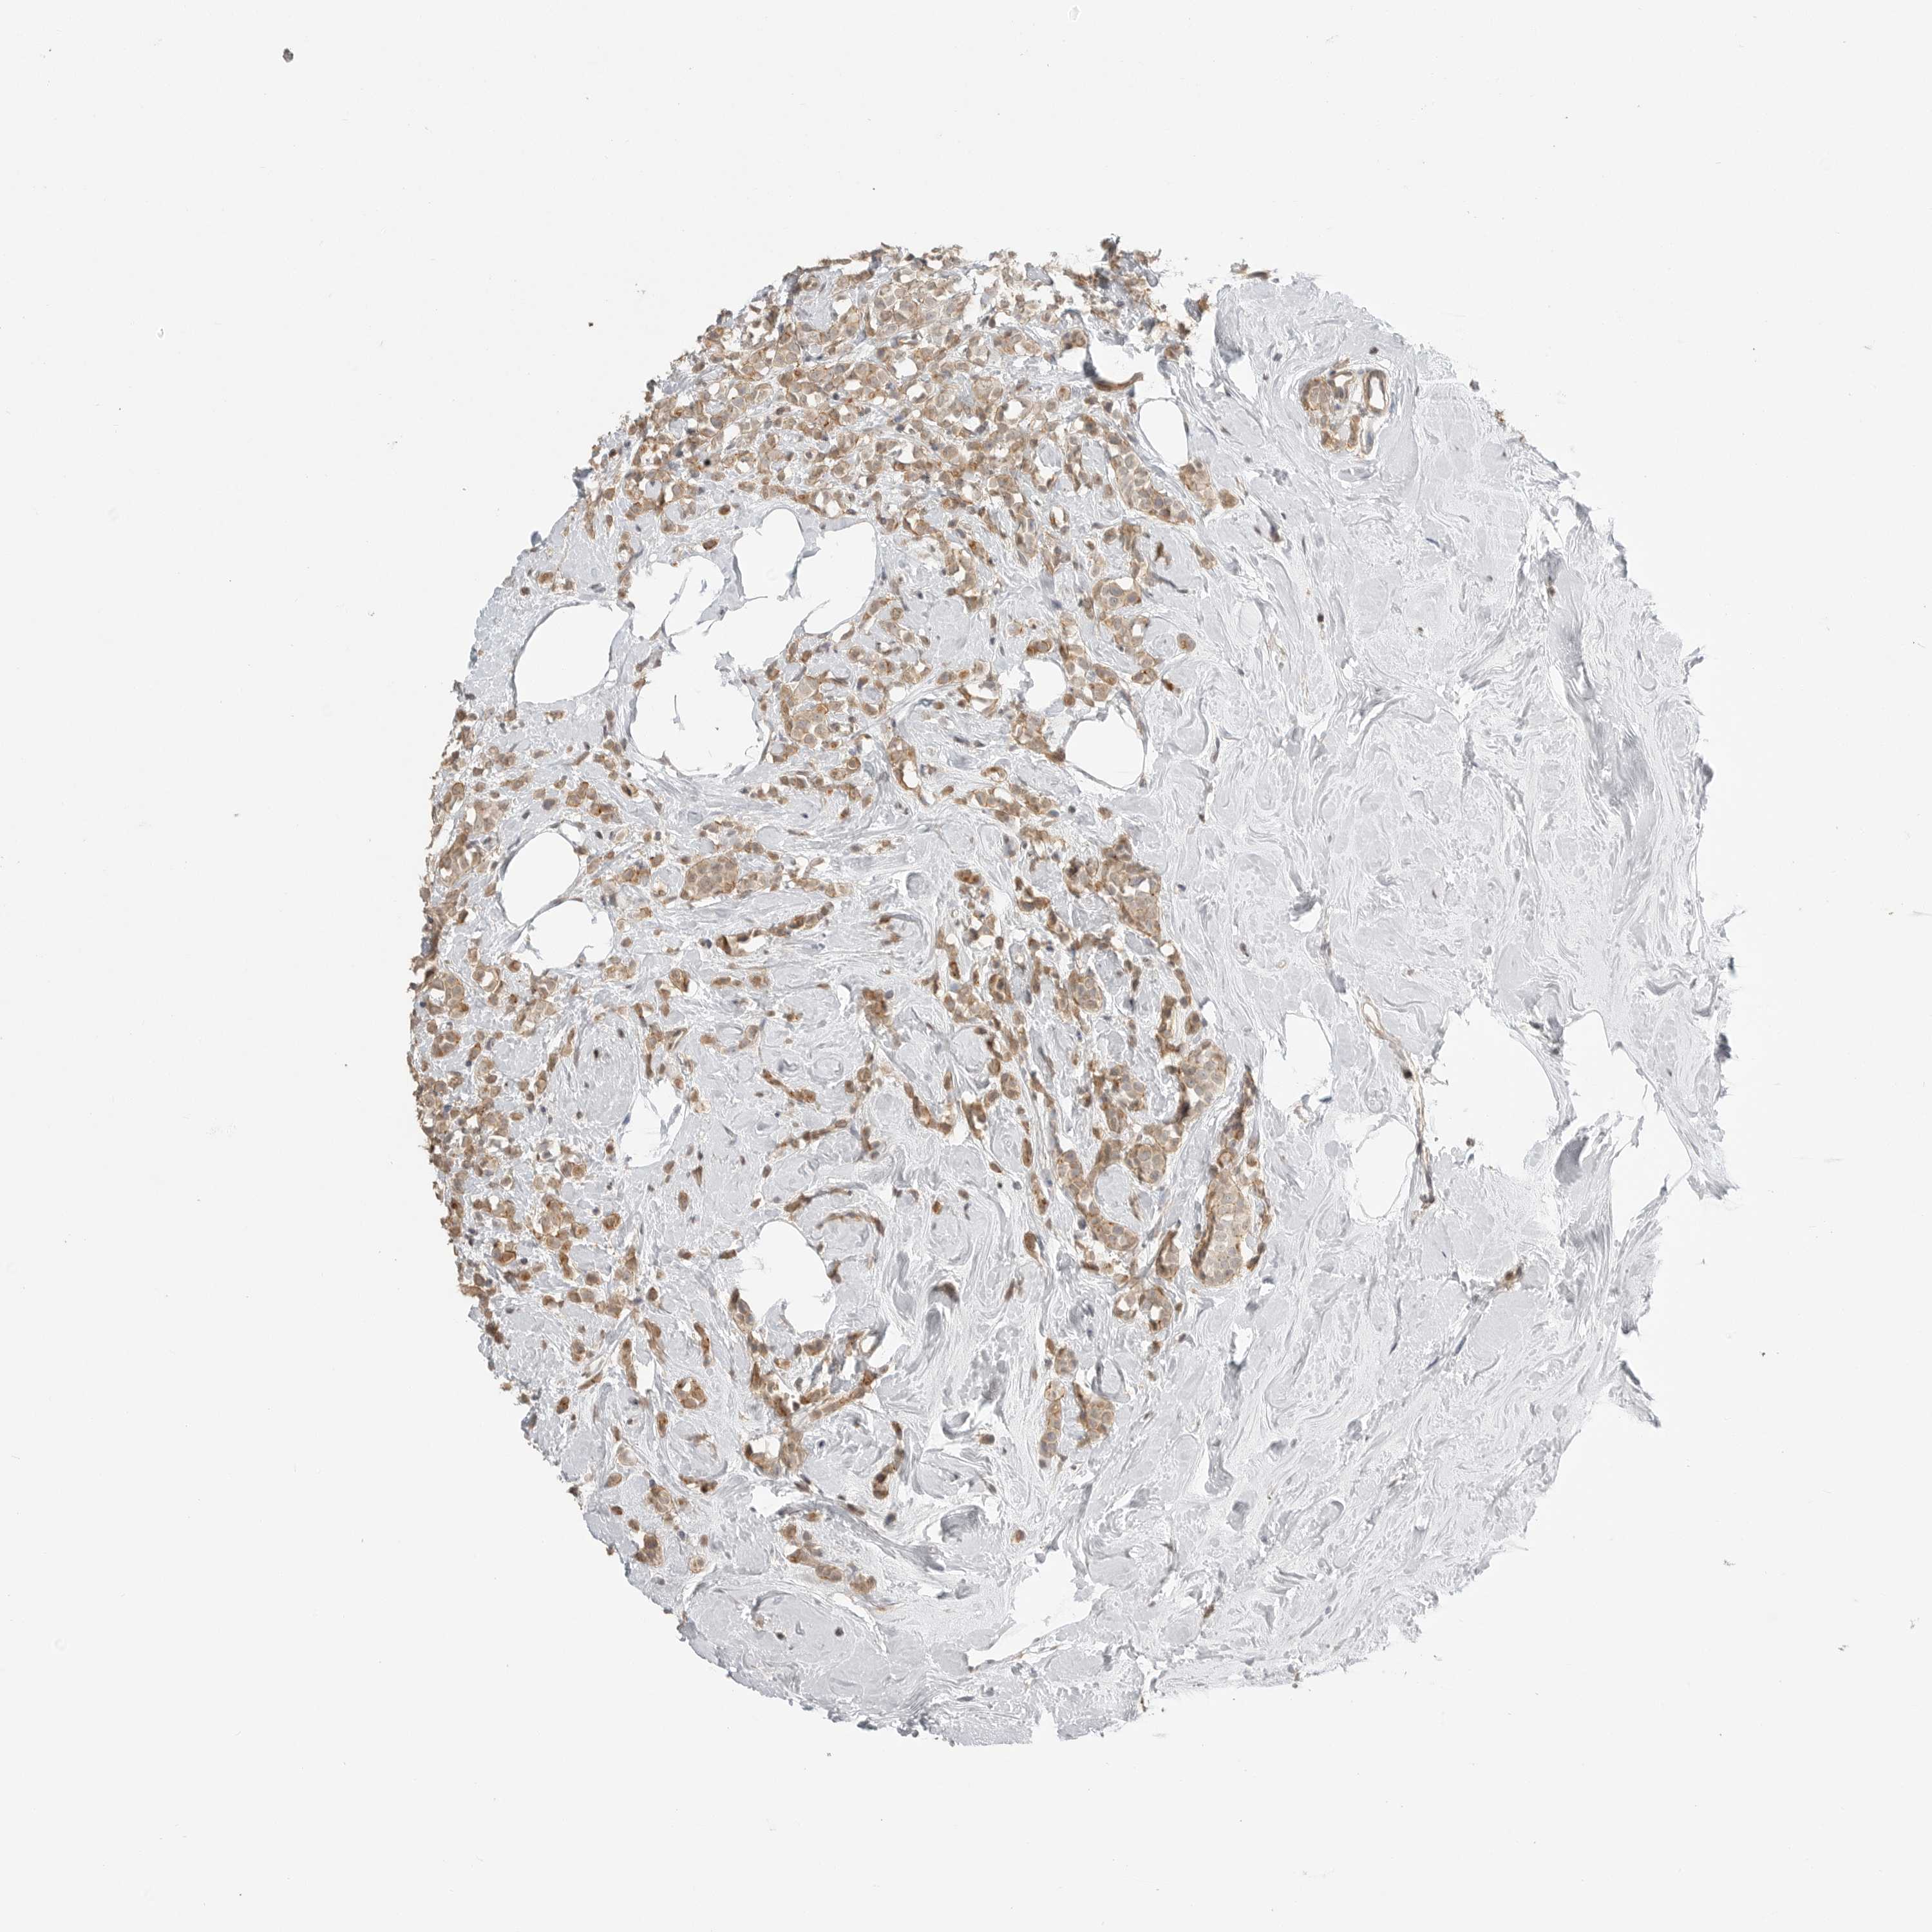

CANCER BREAST CANCER Show tissue menu

BRCA TCGA BRCA VALIDATION PROTEIN EXPRESSION